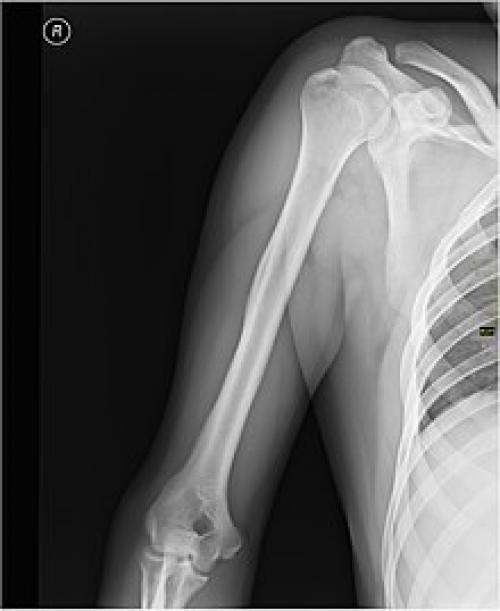

Плечевой сустав. Плечо (часть тела)

В обычном, не-анатомическом словоупотреблении под плечом понимается не «верхняя часть руки», а часть туловища от шеи до руки. Анатомически эта часть соответствует плечевому суставу и надплечью , то есть — поясу верхних конечностей .

Каркасом плеча служит плечевая кость .

При травмах плеча возможно повреждение нервов и сосудов, а также переломы плечевой кости, наиболее частой локализацией которых является шейка плечевой кости.